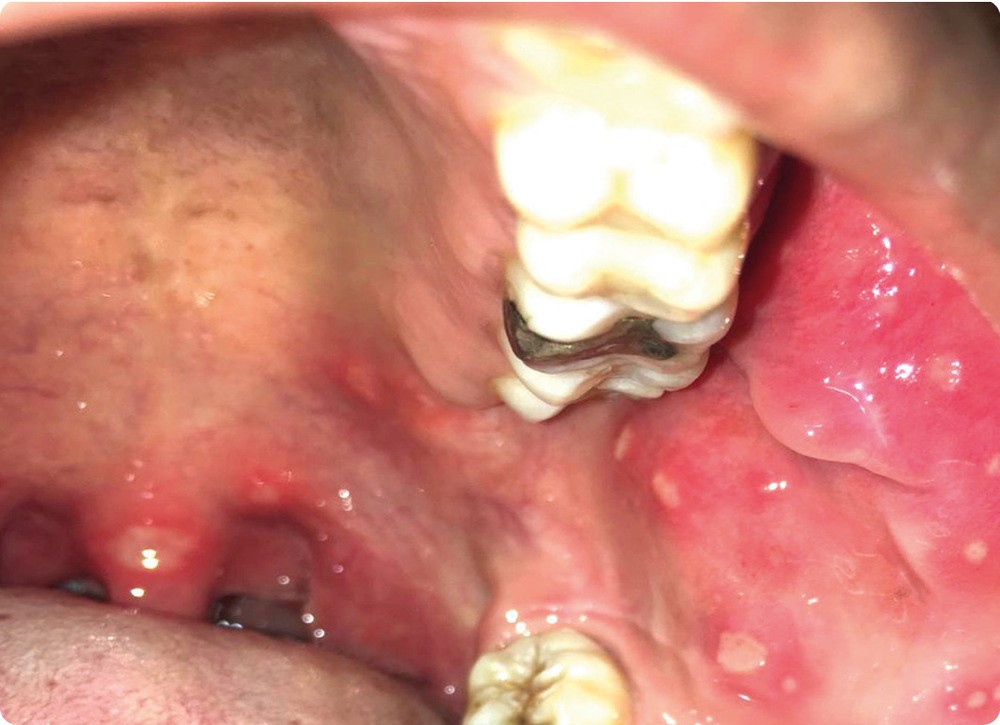

• On observait au niveau endo-buccal de nombreuses lésions typiques d’aphtes d’aspect milliaire ou vulgaire, sur la joue, le palais mou et la luette.